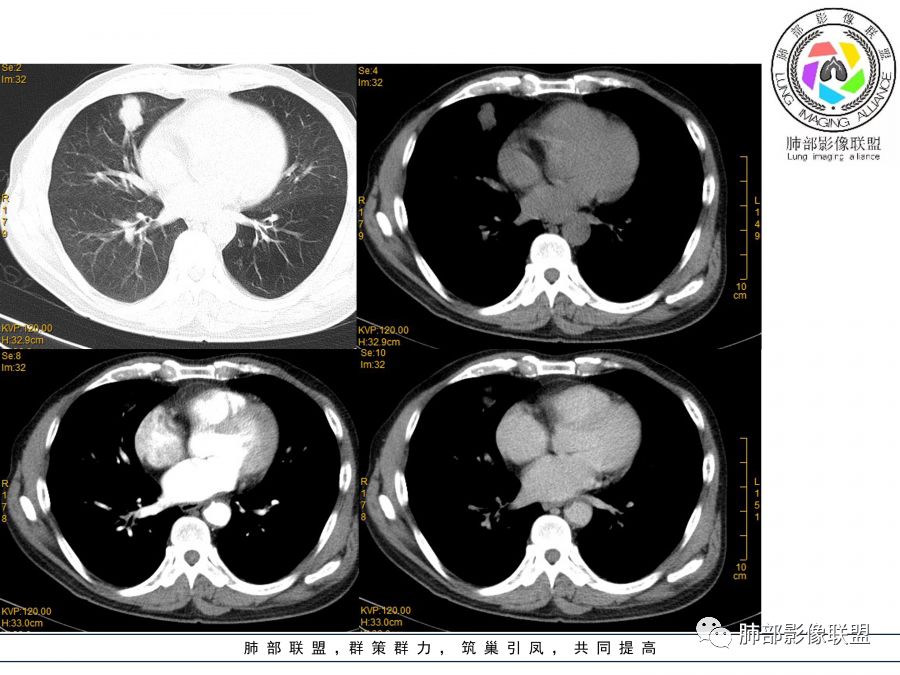

晨读病例  患者老年男性,因腰腹部疼痛3周,排尿困难1周入院。查尿常规及C反应蛋白提示泌尿系感染。肿瘤标志物NSE、细胞角蛋白19片断稍升高。胸部CT:右肺中叶内侧段类圆形肿块影,浅分叶,部分层面见深分叶,胸膜牵拉及支气管截断征象,边界清,密度低,无强化,且垮叶裂。综合考虑恶性病变,类癌及小细胞可能性大,鉴别囊肿等良性病变肺囊肿。

实性还是GGO?      实性

边界清楚、光滑?     光滑清楚,浅分叶,无明显毛刺

与支气管关系如何?   能看清楚吗

看起来堵了

按这个就是堵了

我们一般是找肺动脉,伴行支气管

堵了大方向不支持良性肿瘤

目测这里还是有强化,其余地方强化幅度不是很明显

浅分叶

边缘膨隆

常规会考虑恶性

1.右肺中叶孤立不规则块影,浅分叶,未见液化或钙化,未见毛刺,未见脐凹,未见明显胸膜牵拉。

2.近肺门侧隐约见支气管截止。

3.外侧可见血管进入,病灶局部轻度强化。

上述均不符合光滑类圆形的支气管肺囊肿,也不符合典型的类癌,切不可先入为主。也不符合转移瘤。

4.肺门纵隔未见增大淋巴结。如此体量的肺块,没有增大淋巴结,不符合小细胞肺癌的生物学行为。

5.未见卫星灶,未见支气管增厚,结核也缺少支持点。

综上,应当鉴别的主要为肺鳞癌及结核灶